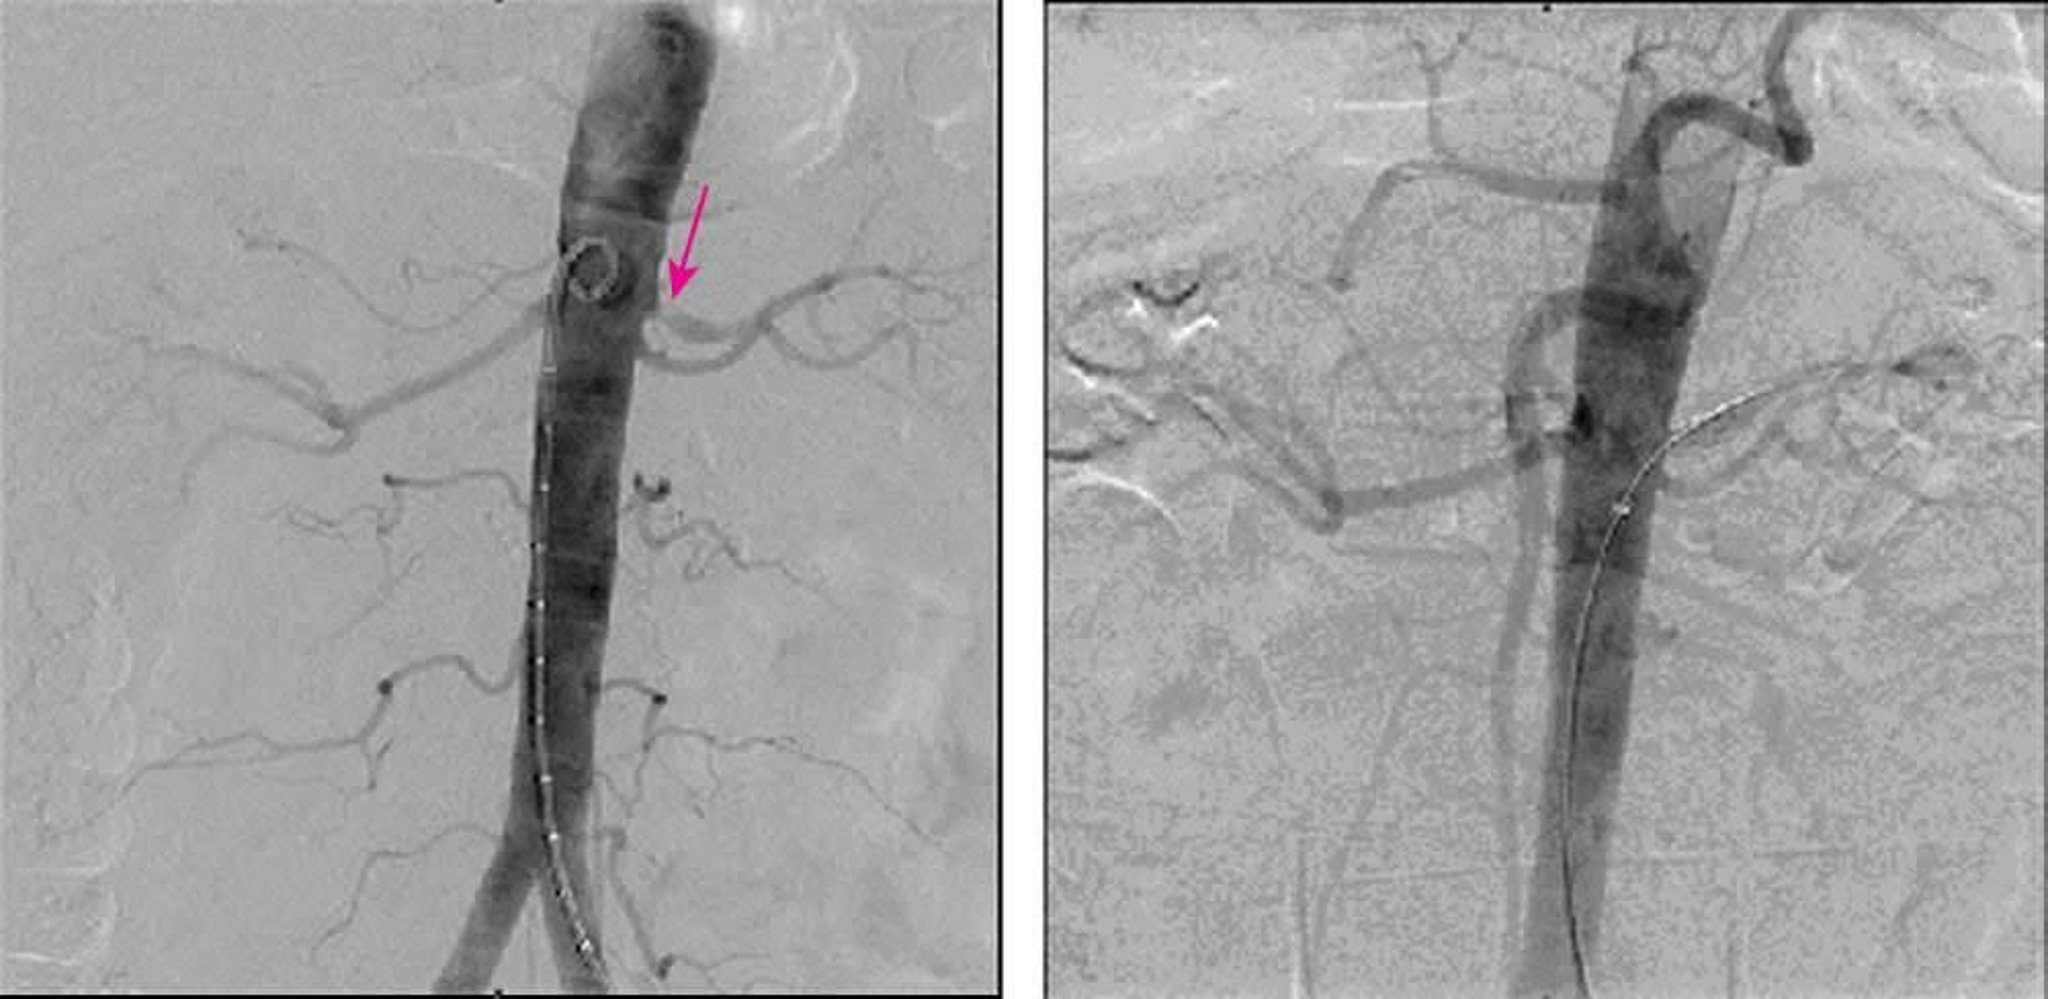

Renal Artery Stenosis (Digital Subtraction Angiography)

The left image shows 90% stenosis at the origin of the left main renal artery on digital subtraction angiography. The right image shows complete resolution of stenosis after stent placement.

Image provided by Jan N. Basile, MD.